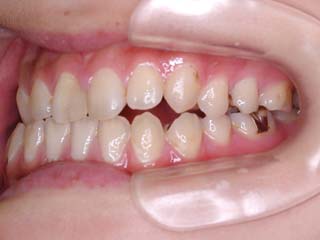

主訴:上の歯が出ている

診断名:顎関節症、上顎前突、叢生を伴う開咬

年齢:20歳

使用した主な装置名:TPB、マルチブラケット装置

抜歯/非抜歯および抜歯部位:抜歯(上顎左右第一小臼歯、下顎左右第二小臼歯)

治療期間:動的処置2年3か月、経過観察3年

費用の目安:保険適応 自己負担金として30~50万

リスク、副作用:外科手術によるリスク、マルチブラケット治療に伴う歯根吸収など偶発症が発生するリスクがある。

比較的強い叢生と、下顎の劣成長を伴う開咬が見られます。成長を終了した永久歯列ですので、骨の大きさのズレへのアプローチは大きく別れる所です。程度が小さければ、歯の傾きで補うように解決しますし、大きなズレであれば、外科的に骨のズレを改善する治療が選択されます。垂直的な問題はその他の不正咬合と比較して、解決が極めて困難な事が多いです。治療後の後戻りが頻繁に見られる不正咬合ですので、外科矯正での改善が望ましい場合も多いでしょう。

術前矯正の仕上げにスプリント治療を行った方が良い場合が多いです。現在、当院での治療では、術前に3か月のスプリント治療を必須にしております。せっかく手術までしてかみ合わせの位置を合わせようとしているのに、顎の関節の位置がずれていたらどうなるでしょう。顎の関節は往々にして顎の大きさのズレをカムフラージュするような偏位を示すので、術後にじわじわと後戻りしているような現れ方で、ズレが見えてくるのでは?このスプリント治療を徹底できたケースでは術後の安定性が極めて高いと感じています。

外科手術は、上顎のインパクションのみをLeFort1にて行いました。